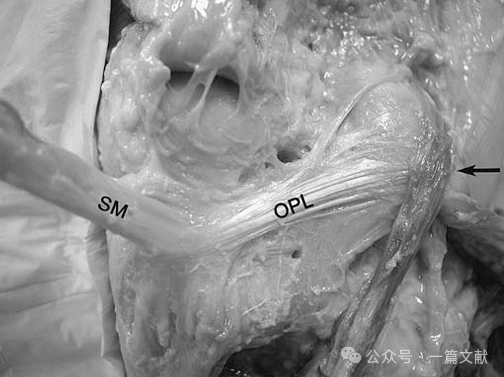

3.腘斜韧带:右膝后侧观显示腘斜韧带(OPL)。其内侧由后斜韧带(POL)的关节囊支与半膜肌(SM)总腱的侧向腱性扩展部融合构成;外侧则附着于腓肠豆区域的关节囊及跖肌止点处(箭头所示)。(注:已移除腓肠肌内外侧头,跖肌保留原位)。